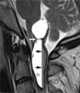

Syringobulbia

Syringobulbia is a medical condition in which syrinxes, or fluid-filled cavities, affect the brainstem. This defect normally results from congenital abnormality, trauma or tumor growth. [Source: Wikipedia ]